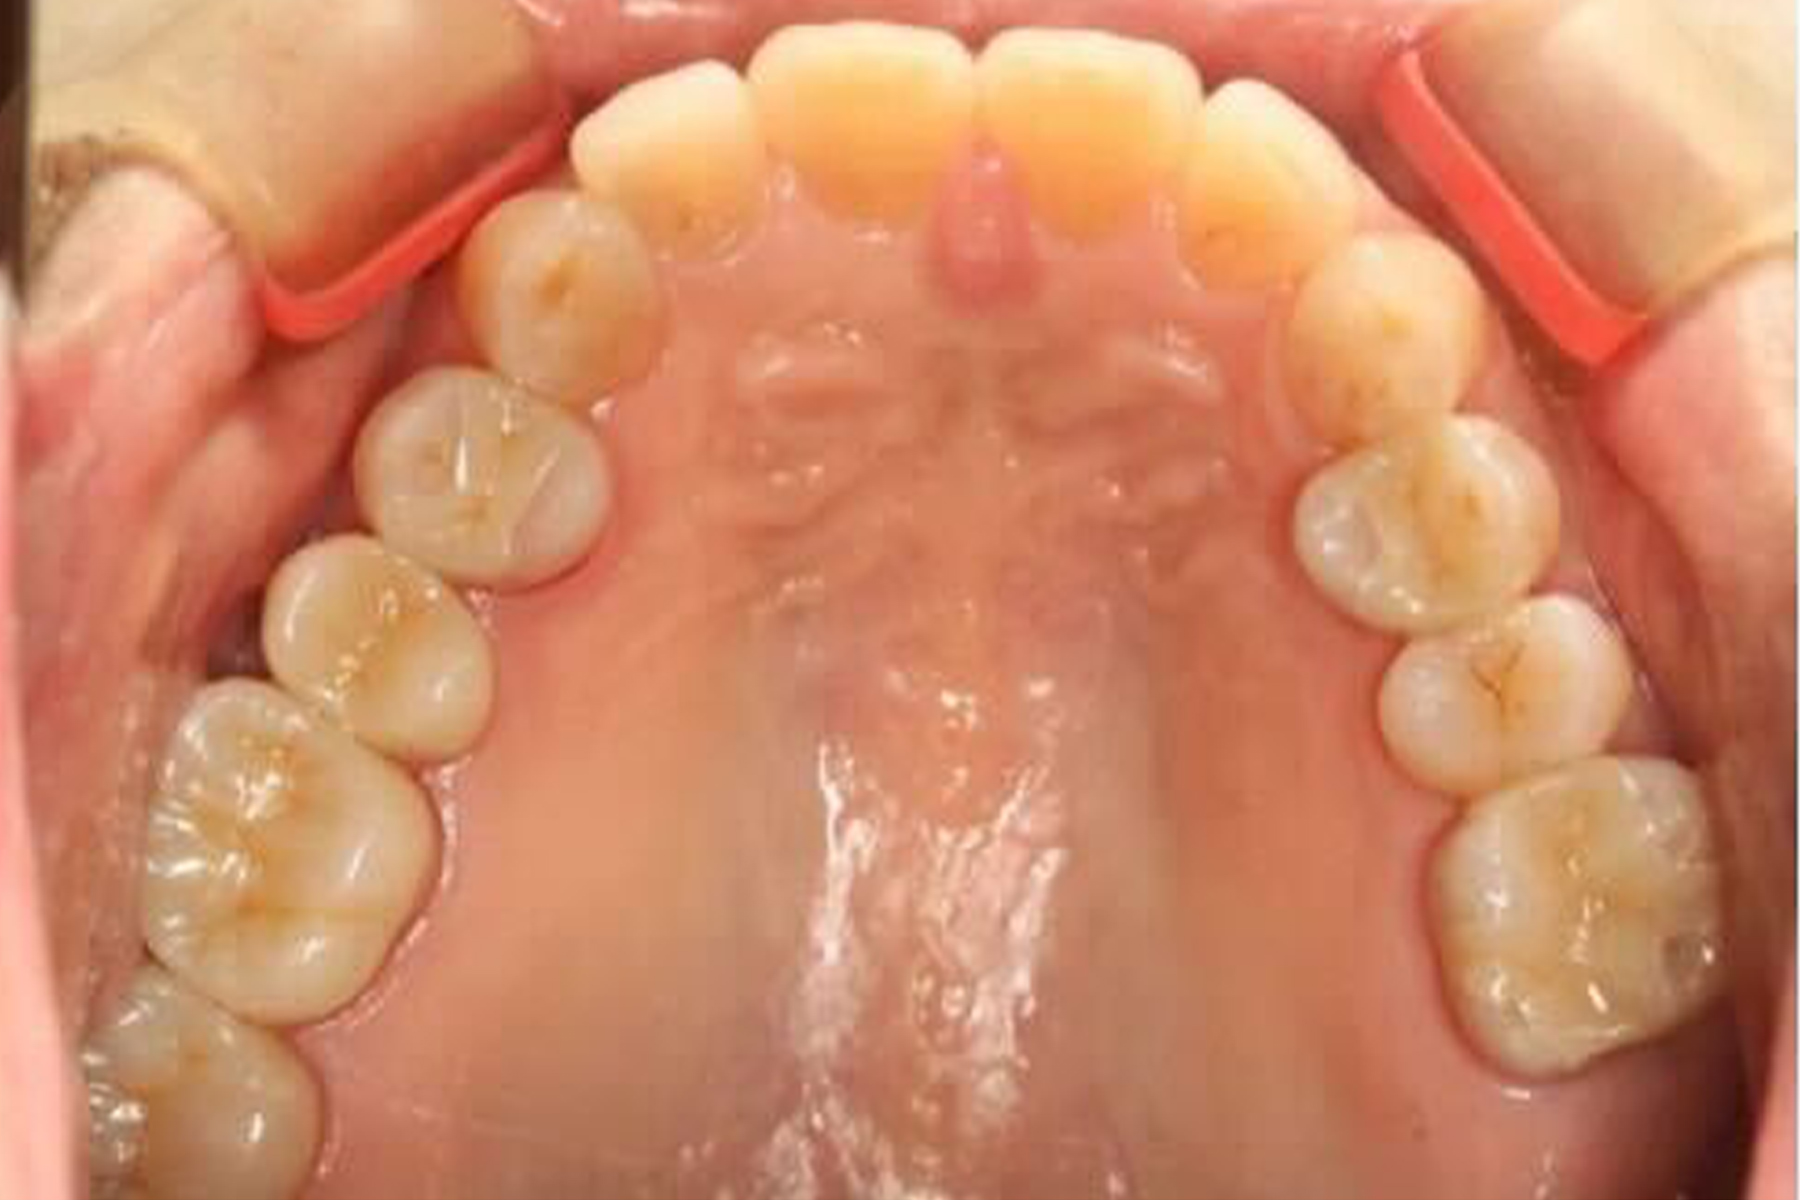

AFTER

| 主訴 | 銀歯を白い歯に変えたい |